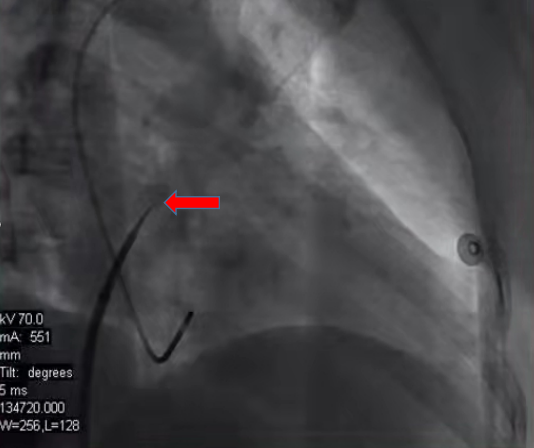

??传统的房颤射频消融术从股静脉穿刺导管入路到房间隔穿刺、射频治疗,都依赖于X射线透视下进行操作,透视时间长、射线量大,并且定位是通过二维的形式展现。但是穿刺位点解剖位置及结构并不能够在X线影像完美呈现。

??红色箭头所示的穿刺点无法准确判定是否为最佳穿刺点,安全性、可靠性较差。穿送过去之后,还需要造影证实,且需要多体位左心房—肺静脉造影,判断肺静脉解剖形态。